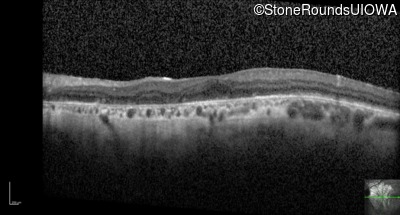

Optical Coherence Tomography - Left - 20/200

Exemplar / OCT Stack